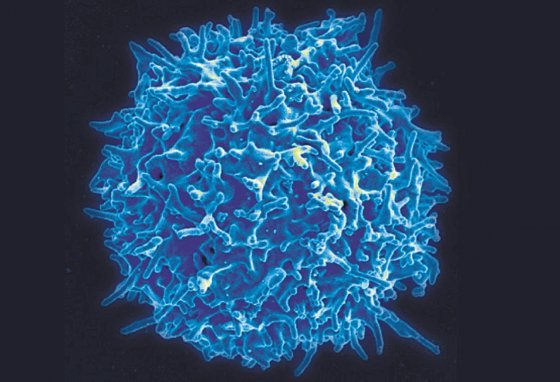

T세포. 미국 국립알레르기·전염병연구소 제공종양은 발달 정도에 따라 대표적인 면역세포인 T세포를 비롯해 주변 면역세포를 무력화시키는 물질을 분비한다. 면역세포 뒤로 자신의 정체를 숨기는 것처럼 면역체계를 약화시키면서 성장하는 것이다. 이 같은 이유로 면역 항암제는 일부 암 환자에게만 효능을 보이는 한계가 있다.

T세포. 미국 국립알레르기·전염병연구소 제공종양은 발달 정도에 따라 대표적인 면역세포인 T세포를 비롯해 주변 면역세포를 무력화시키는 물질을 분비한다. 면역세포 뒤로 자신의 정체를 숨기는 것처럼 면역체계를 약화시키면서 성장하는 것이다. 이 같은 이유로 면역 항암제는 일부 암 환자에게만 효능을 보이는 한계가 있다.

T세포. 미국 국립알레르기·전염병연구소 제공

T세포. 미국 국립알레르기·전염병연구소 제공김인산 KIST 책임연구원은 2020년 여러 암 종류에서 면역세포를 효과적으로 활성화시키는 나노 입자를 개발했다. 연구팀은 일부 암 환자에게만 효능을 보이는 면역 항암제의 한계를 극복하기 위해 엑소좀에 주목했다. 엑소좀은 세포가 방출하는 나노미터 크기의 입자로 혈액 응고나 세포 간 신호 전달, 폐기물 관리 같은 과정에 중요한 역할을 한다. 연구팀은 엑소좀을 이용해 면역세포가 암을 적(敵)으로 인지하도록 만들었다. 엑소좀 나노입자를 이용한 실험에서 유방암과 대장암 등 여러 종양 모델에 항암 효과가 확인됐다. 연구팀은 “엑소좀은 산성을 띠는 암세포와 특이적으로 융합해 암세포 표면에 표적 신호를 만든다”며 “표적 신호가 만들어진 암세포는 면역세포로부터 더 이상 숨지 못한다”고 설명했다.